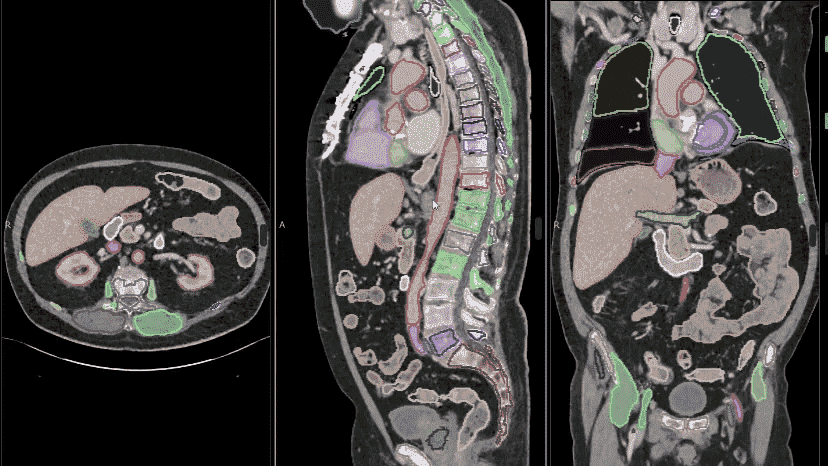

利用NVIDIA VISTA-3D NIM微服务实现计算机断层扫描器官和疾病分割NVIDIA Research已经开发出一种新模型,用于分割全身CT图像,并将其封装到一个高度优化的容器中,该容器可以在部署时进行扩展。本文…